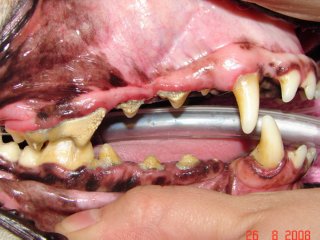

In stage IV (severe periodontitis) there is severe gum recession, bone loss and root exposure. The periodontal supporting structures are almost entirely destroyed and the teeth are mobile. Bacteria may be spreading throughout the entire body via the bloodstream and may damage the kidneys, liver and heart.

While periodontal disease is irreversible, treatment at any point in the disease process will stop or slow this progression. Without treatment, the end stage of this disease is tooth loss; however the disease has likely caused problems well before this. Bacteria from infected gums might gain access to the systemic circulation. Consequences of bacteria circulating in the main blood stream include kidney infections, liver abscesses, infectious arthritis, and birth problem in puppies. These bacteria may also become attached to heart valves and cause endocarditis which results in an intermittent infection and strokes. Clinical signs of gingivitis are swelling, a gingival color change from pink to red, bleeding gums, significant tartar, and bad breath. Clinical signs of periodontitis include the above plus gum recession, difficulty eating, and increased tooth mobility.